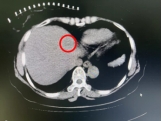

术中影像

病灶 毗邻心脏

60岁的胡女士因结肠癌于2023年1月接受了肝左外叶切除+右半结肠切除+肝右叶肿瘤切除手术,2023年12月复查时发现肝脏出现新的占位,考虑为术后肝内多发转移,一处病灶靠近心脏位置,另外一处病灶靠近肾脏,如若再次手术,不仅创伤大,而且对术后病人的康复不利,胡女士慕名来到我院介入科,团队通过仔细评估并组织讨论,与胡女士及家属充分沟通,决定采用“复合式冷热消融术”创新治疗方法。